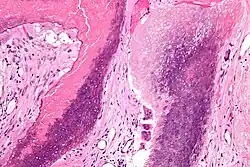

Histopathology of pilomatricoma, high magnification, H&E stain, showing the characteristic components of basaloid cells and ghost cells.

The characteristic components of a pilomatricoma include a stroma of fibrovascular connective tissue surrounding irregularly shaped, lobulated islands containing basaloid cells (being darkly stained, round or elongated, with indistinct cell borders and minimal cytoplasm, with nuclei being round to ovoid, deeply basophilic and generally prominent nucleoli), which abruptly or gradually transitions into ghost cells (having abundant, pale, eosinophilic cytoplasm, well defined cell borders and a central clear area, but only faint traces of nuclear material), which in turn may transition into keratinaceous to amorphous necrosis.[11]

The presence of calcifications with foreign-body giant cells is common within the tumors.[12]